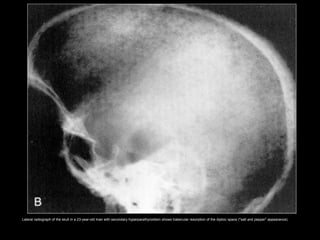

Lateral radiograph of the skull in a 23-year-old man with secondary hyperparathyroidism shows trabecular resorption of the diploic space ("salt and pepper" appearance).

Lateral radiograph ofthe skull in a 23-year-old man with secondary hyperparathyroidism shows trabecular resorption of the diploic space ("salt and pepper" appearance).